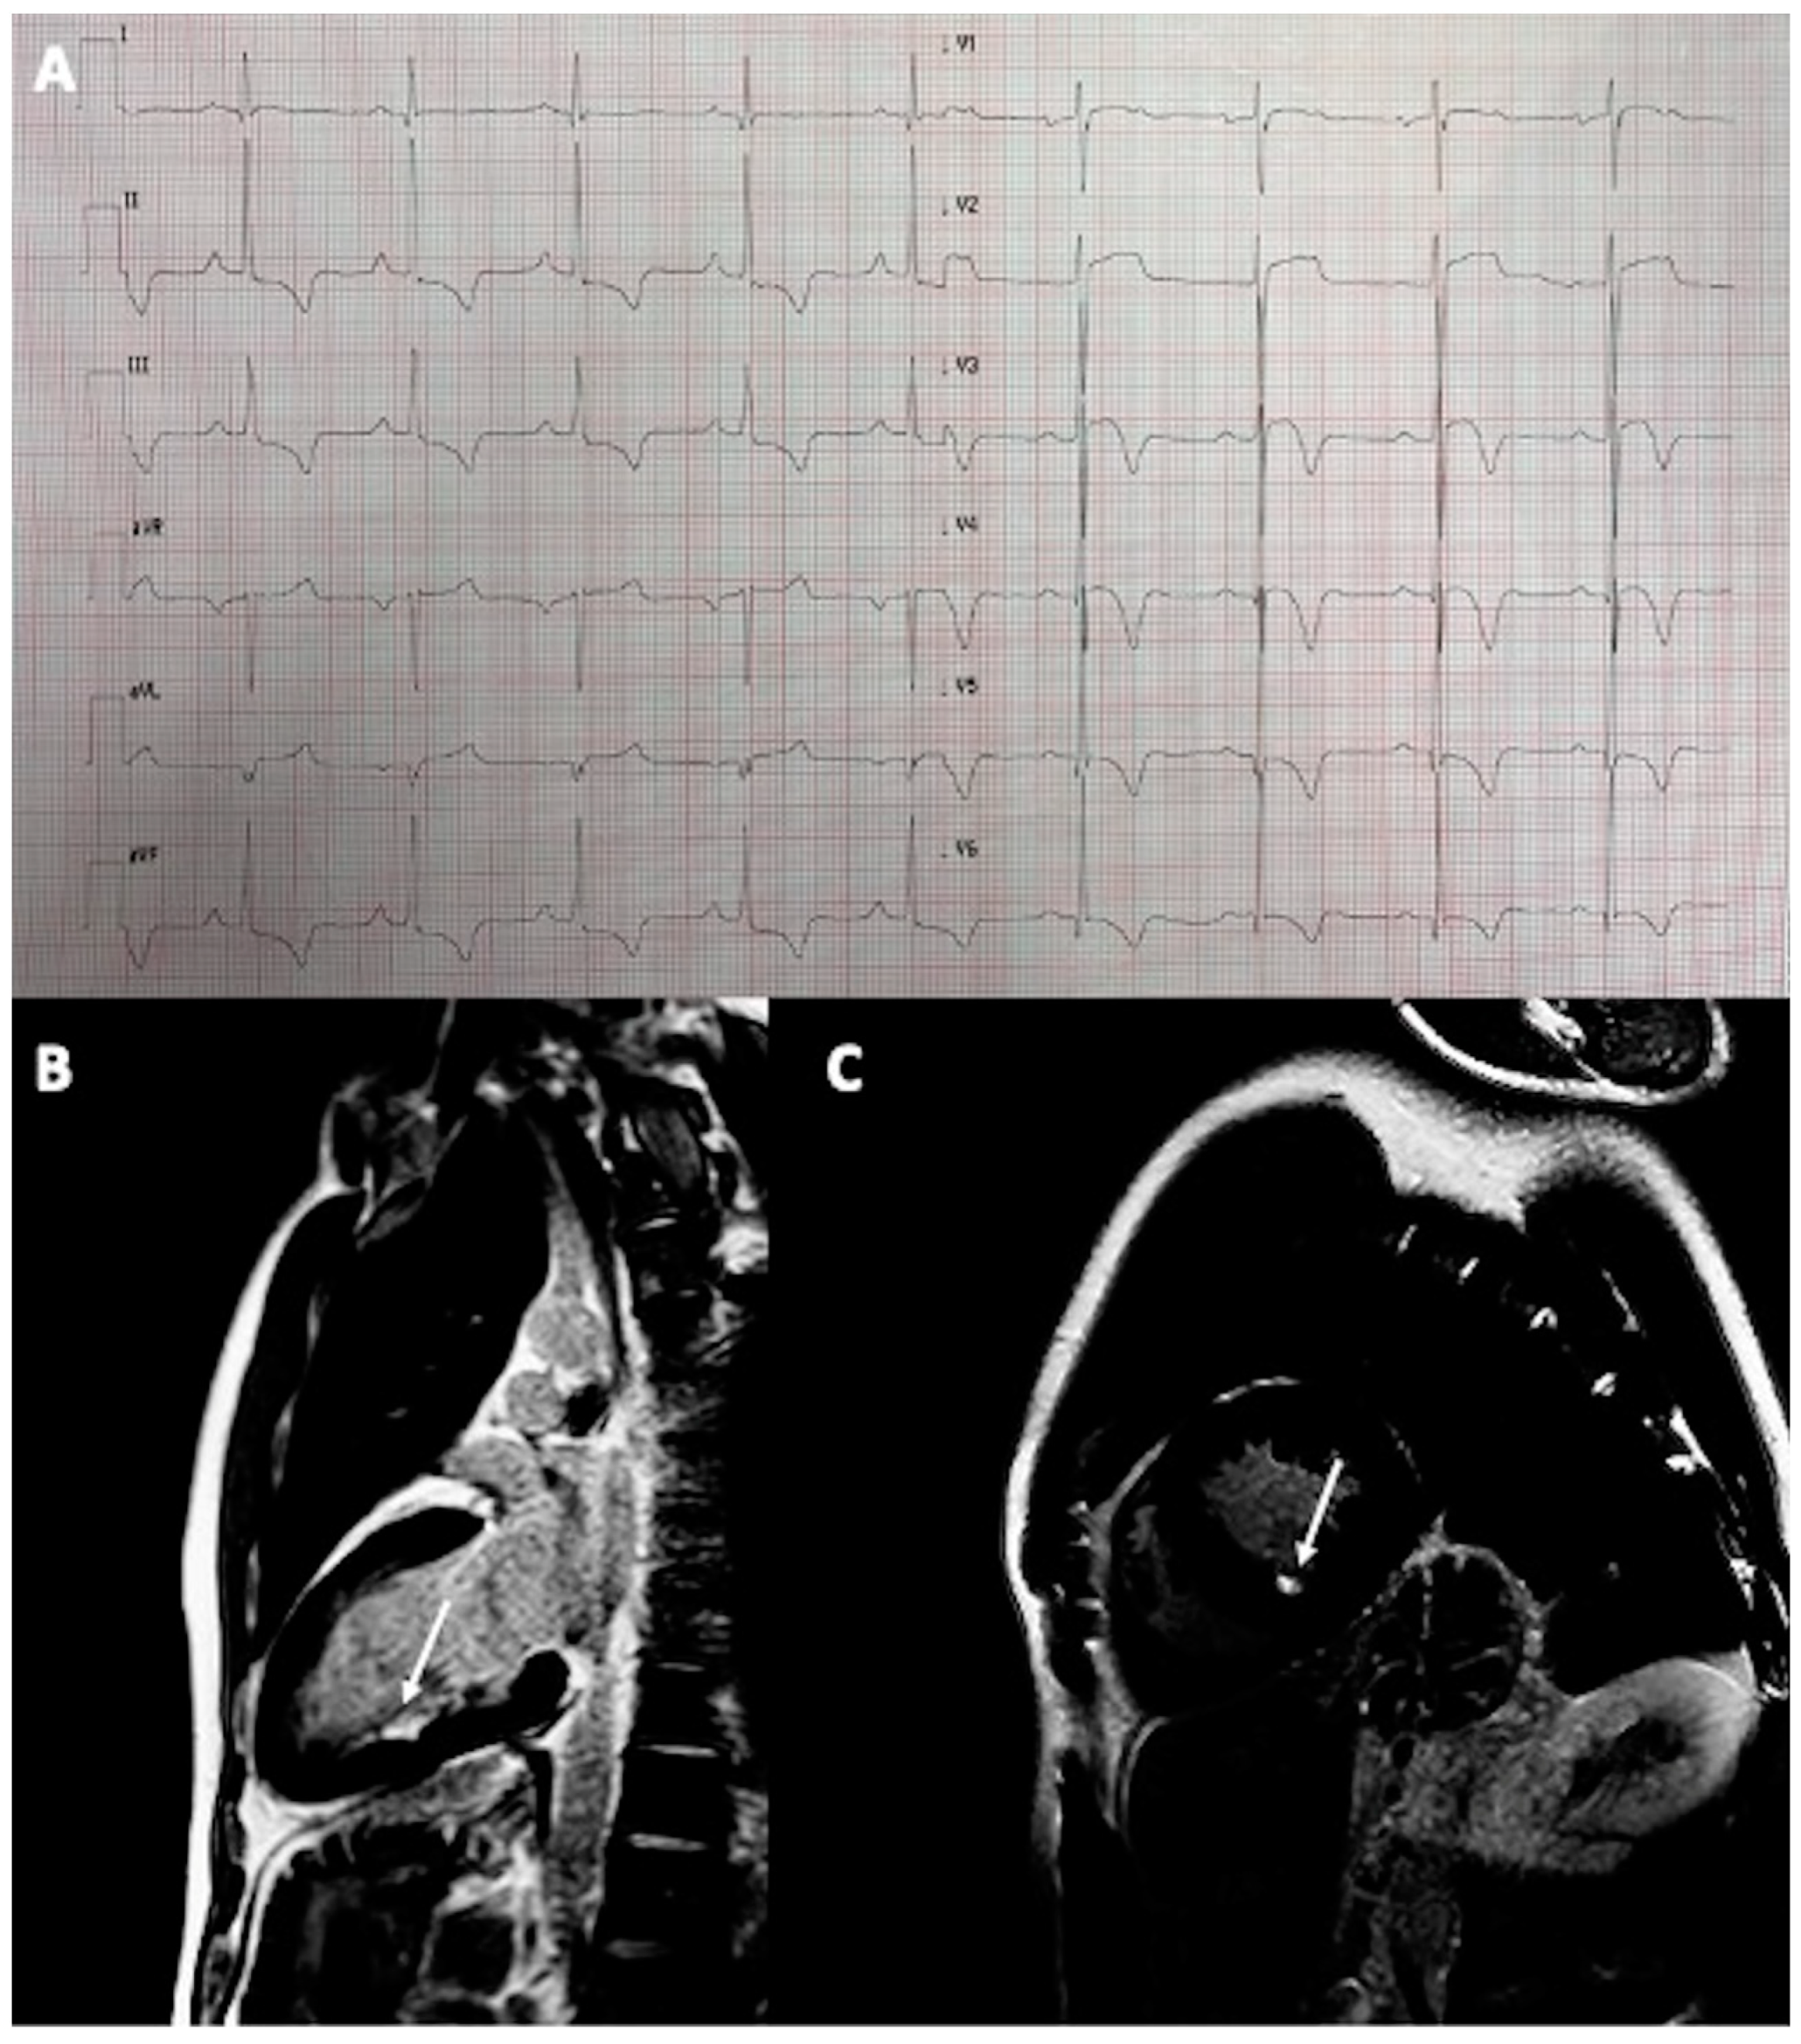

A 36-year-old male semi-professional runner was referred for examination after collapsing at the finish of a half-marathon run. He had a 15-year-long history of long-distance running without symptoms. His ECG revealed signs of left ventricular hypertrophy (LVH) with left atrial enlargement and T-wave inversions in leads II, III, aVF, V3–V6 with an ST-segment depression of 1 mm in leads II, III, and aVF (Figure 2A). Transthoracic echocardiography revealed asymmetric hypertrophy of the interventricular septum of 17 mm suggestive of hypertrophic cardiomyopathy (HCM). The patient had no family history of HCM. CMR confirmed the diagnosis, showing also a mild left ventricular outflow tract obstruction (LVOTO) with systolic anterior movement (SAM) of the anterior mitral valve leaflet. There were no signs of non-ischemic LGE but there was a small subendocardial scar in the hypertrophied interventricular septum (Figure 2B,C), typical for prior small myocardial infarction. The patient had no signs of coronary artery disease on the CTCA. Other possible causes of secondary cardiac hypertrophy have been excluded, as per the guidelines on the diagnosis and treatment of hypertrophic cardiomyopathy [13]. Therefore, the MI was most probably attributable to a mismatch between oxygen demand and supply during intensive exercise. The patient was advised to refrain from competitive, strenuous exercises and was put on a small dose of beta-blocker.

Figure 2.

A 36-year-old male athlete with HCM and MI: (A) Electrocardiogram showing signs of LVH described above; (B,C) Cardiac magnetic resonance demonstrating small subendocardial scar in the interventricular septum (arrows).